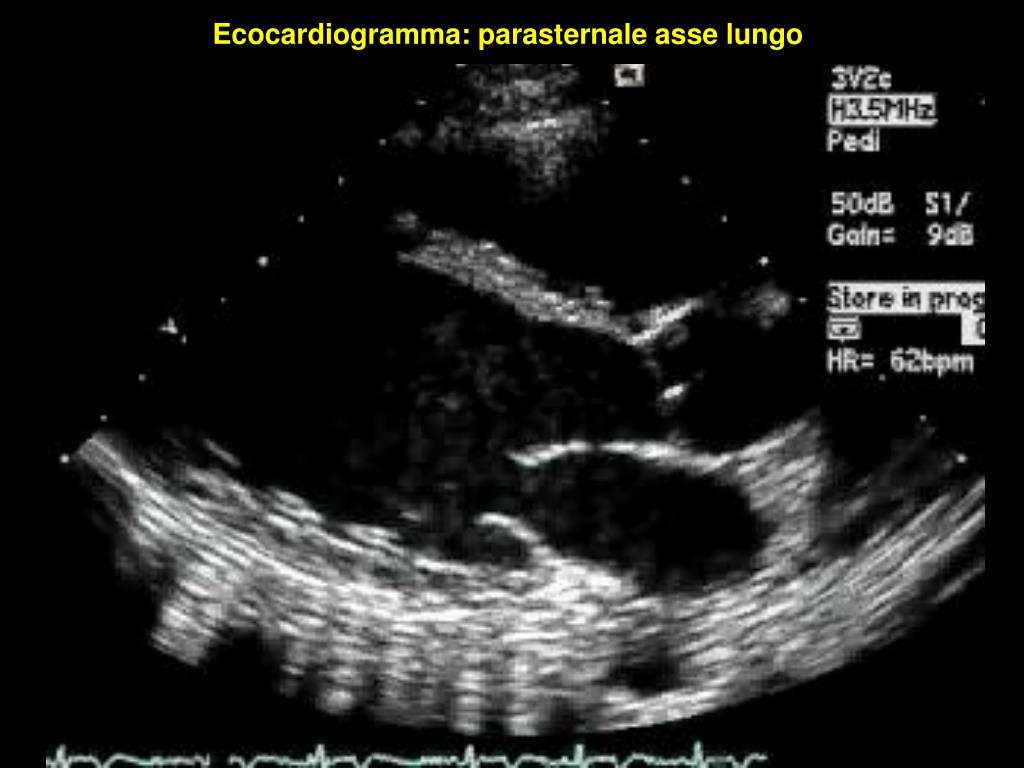

30. Ecocardiogramma: parasternale asse lungo